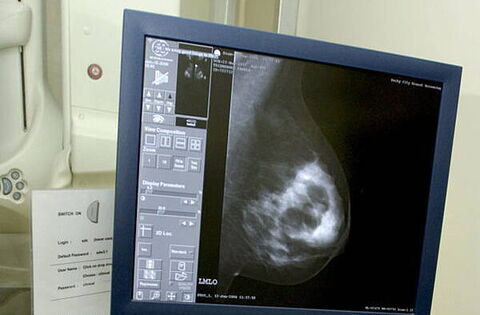

Mother of three Aine McSweeney from Clonmel, Co Tipperary, also claims that she had two mammograms in 2020 and 2022, which she says were allegedly incorrectly interpreted as benign.

In the proceedings, it is claimed that Ms McSweeney had two mammograms at the Breast Clinic in University Hospital Waterford in 2020 and 2022, which were reported back as benign.

It is claimed that these should have been reported as being indeterminate. It is contended that the two mammograms allegedly showed clustered calcifications. If the two mammograms had been followed through, the McSweeny side contends there would have been an investigation and treatment.

In the proceedings, it was claimed that an alleged incorrect interpretation was given in a radiology report of a mammogram of October 23, 2020 and that the findings were reported as benign when it is claimed it showed clustered microcalcifications in the left breast and allegedly should have been reported as being indeterminate.

It was further claimed there was an alleged incorrect interpretation of a January 7, 2022 mammogram, which was reported as benign and which, it is claimed, should also allegedly have been reported as being indeterminate.